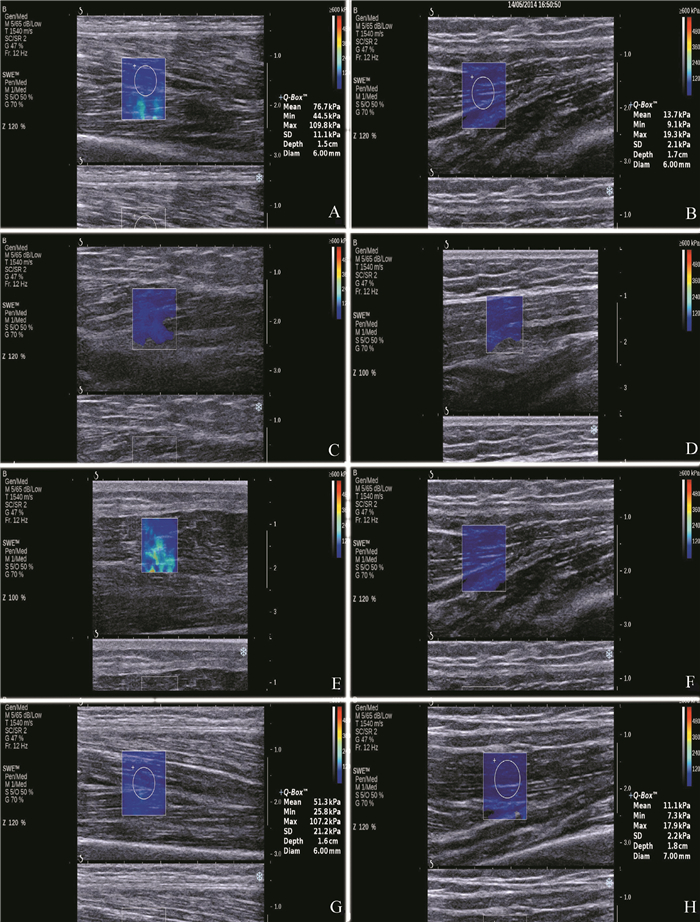

治疗前观察组患者患侧与正常对照组相应一侧下肢相关肌肉的杨氏模量比较差异均有统计学意义 (P均 < 0.01);观察组患者患侧治疗后股外侧肌、股内侧肌、股直肌及股二头肌杨氏模量值均较治疗前下降 (P均 < 0.05),见表 2及图 1。

图 1 观察组与正常对照组肌肉超声弹性图 A:正常对照组股外侧肌超声弹性图,图中方框为感兴趣区位置,方框中的圆为Q-box,图的右侧显示弹性模量具体测量数值,包括杨氏模量平均值 (76.7 kPa)、最小值 (44.5 kPa)、最大值 (109.8 kPa) 及标准差 (11.1 kPa)、深度 (1.5 cm) 以及Q-box直径 (6.0 mm)。B:观察组股外侧肌超声弹性图,杨氏模量平均值 (13.7 kPa)、最小值 (9.1 kPa)、最大值 (19.3 kPa) 及标准差 (2.1 kPa)、深度 (1.7 cm) 以及Q-box直径 (6.0 mm)。C:正常对照组股内侧肌超声弹性图,杨氏模量平均值 (9.3 kPa)、最小值 (7.6 kPa)、最大值 (17.5 kPa) 及标准差 (2.1 kPa)、深度 (1.6 cm) 以及Q-box直径 (6.0 mm)。D:观察组股内侧肌超声弹性图,杨氏模量平均值 (22.9 kPa)、最小值 (12.3kPa)、最大值 (27.6kPa) 及标准差 (2.1 kPa),深度 (1.7 cm) 以及Q-box直径 (6.0 mm)。E:正常对照组股直肌超声弹性图,杨氏模量平均值 (10.2 kPa)、最小值 (7.41 kPa)、最大值 (13.7 kPa) 及标准差 (2.1 kPa)、深度 (1.7 cm) 以及Q-box直径 (6.0 mm)。F:观察组股直肌超声弹性图,杨氏模量平均值 (19.7 kPa)、最小值 (13.3kPa)、最大值 (32.6kPa) 及标准差 (2.1 kPa)、深度 (1.7 cm) 以及Q-box直径 (6.0 mm)。G:正常对照组股二头肌超声弹性图,杨氏模量平均值 (51.3 kPa)、最小值 (25.8 kPa)、最大值 (107.2 kPa) 及标准差 (21.2 kPa)、深度 (1.6 cm) 以及Q-box直径 (6.0 mm)。H:观察组股二头肌超声弹性图,杨氏模量平均值 (11.1 kPa)、最小值 (7.kPa)、最大值 (17.kPa) 及标准差 (2.2 kPa)、深度 (1.8 cm) 以及Q-box直径 (7.0 mm) |